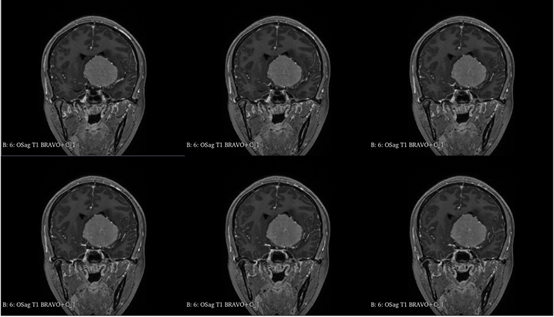

入院查体:神志清,精神可,言语流利,左侧瞳孔4mm>右侧瞳孔3.5mm,右侧对光反射存在,间接对光反射消失,左侧直接对光反射消失,间接对光反射存在,左眼失明,右侧鼻唇沟浅,四肢肌力及肌张力大致正常,双侧巴氏征未引出,颈软。

入院诊断:颅内占位病变(前颅窝底)脑膜瘤?;左眼失明;鼻炎

前颅窝底脑膜瘤常起源于前颅底筛骨筛板处的硬膜,瘤体多为双侧生长,少数为偏侧生长,女性稍多于男性。肿瘤可累及鸡冠和蝶骨平台的任何区域,是前颅窝肿瘤中最多见的一种。因为肿瘤位于前颅窝底,额叶在功能上属于“哑区”,患者就诊发现肿瘤时瘤体多已巨大。主要症状可有颅内压增高症状、视力减退、癫痫以及精神症状等。该患者主因“左眼失明10个月,头痛3个月”就诊。术中采用双额冠状开颅,左侧为主,由于肿瘤体积巨大,术中切除少许薄层额叶脑组织,边离断基底、边瘤内减压,分块切除肿瘤,最终探查肿瘤基底主要位于鸡冠、筛板、蝶骨平台、鞍结节、前床突处硬膜,术中见肿瘤供血主要来源于前颅窝底硬膜及大脑前动脉分支,术中仔细辨认供血动脉、过路血管,大脑前动脉及其分支保护完好,术中见视神经、视交叉受压明显,尤其是左侧视神经已缺血苍白,最终达Simpson II级切除。术者体会,该患者术前行多模态重建,可见瘤表数条粗大的静脉,术中切莫过早离断肿瘤的引流静脉,以防因引流不畅致瘤体肿胀出血;术前行多模态重建,利于鉴别供血动脉、过路血管,早期离断供血动脉更利于肿瘤切除;该类肿瘤基底一般较为广泛,不能盲目离断基底,尤其是近鞍结节处,可以于中线处离断基底,进入第一间隙后向两侧探查并保护视神经,待充分缩小瘤体看清楚毗邻的血管神经后再将其完全切除;术毕做好多层颅底重建以防脑脊液漏。另外,该患者术前左眼失明已达10个月,术后第1天即有光感,术后1月复查左眼视力可达50cm内数指,这在临床中非常少见,对于此类病人,不要轻易放弃挽救视力的任何机会。